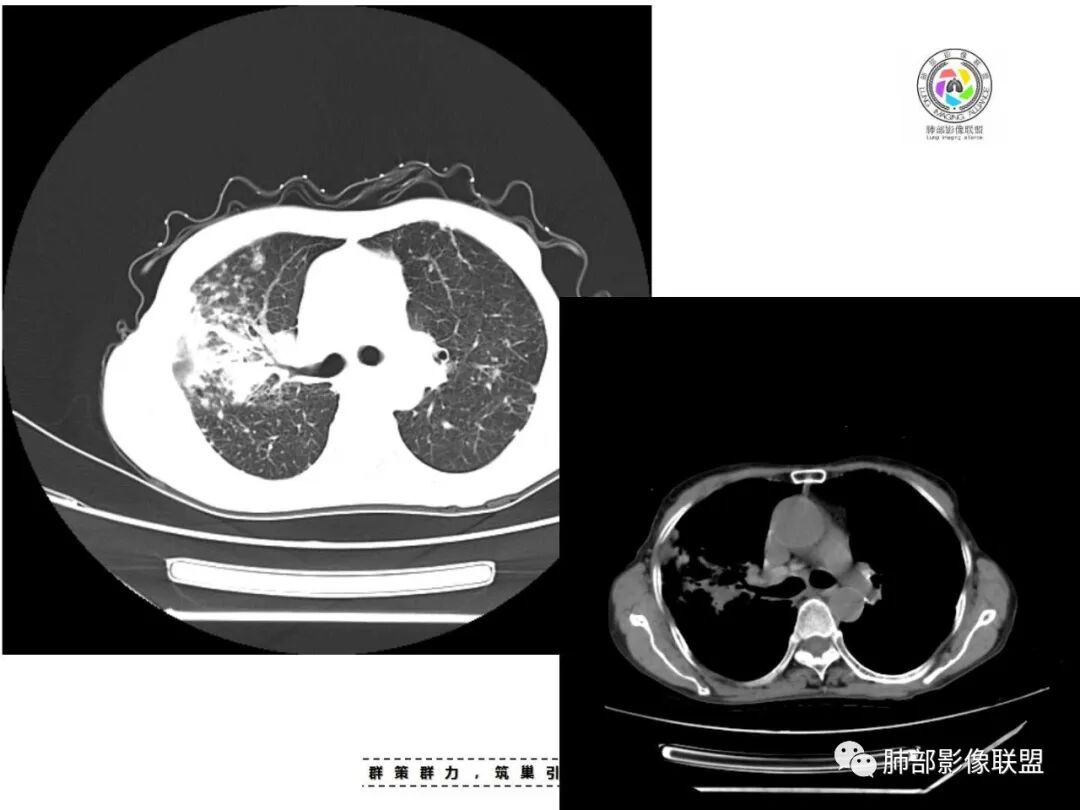

双肺多发斑片,索条及结节影,内可见钙化,右肺上叶后段支气管截断,断端圆钝略扩张,双肺门及纵膈淋巴结钙化,双侧胸膜增厚伴钙化。首先考虑结核。右肺上叶亚段气管分叉处结节,警惕肿瘤

老年女性,双肺索条纤维影,右肺上叶散在卫星灶,树芽征,小叶中心融合,右肺后段支气管圆形截断,实变病灶内支气管扩张,考虑结核。

两肺上叶多发索片小结节影,部分密度较高,中央间质和周围间质都增厚,肺门纵隔淋巴结肿大钙化,基础疾病考虑有尘肺或陈旧结核,需结合相关病史;右肺上叶见斑片点片状模糊影,部分树芽征上叶后段局部细支气管闭塞,考虑感染,结核可能性大,右肺上叶后段病灶实变成团块状,密度低于胸壁肌肉,首先还是考虑结核肉芽肿,治疗后复查除外合并肿瘤可能。

患者老年女性,亚急性起病,主要症状表现为咳嗽、咳痰半月余,查体:双现呼吸音粗,双肺可闻及痰鸣音。胸部CT:双上肺胸膜下可见多发小叶实变影,双上肺可见多发小叶中心性结节及小叶间隔增厚,右上肺后段可见亚段性实变影,内见多发空洞,前段可见GGO及树芽征,后段局部支气管闭塞,肺门淋巴结肿大并钙化。病灶整体:有气道、间质播散,一元论考虑肺结核合并支气管结核可能性大,建议好好查痰;这样病灶:明显实变+空洞+气道播散,若是结核,痰涂片找到抗酸杆菌应该没问题。建议支气管镜检查助诊,了解有无支气管结核及合并腺癌的可能。

1.双肺片状影、大小不等斑片影、结节影、树芽等,病灶密度偏高多钙化。

2.病灶上肺为主,胸膜下分布为主。双肺病灶明显不对称,右肺块状影较大。

3.纤维条索影广泛杂乱、牵拉,横向分布为主,这点给人也印象很深!

4.纵隔轻度右移。双肺门纵隔淋巴结增大钙化。